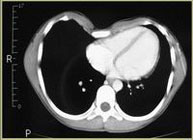

Pectus Excavatum Pectus Excavatum Asimétrico Índice de Asimetría 0.6 (+R/-L)(|AI|> 0.05 Asimétrico) Índice de Haller 4.5 (HI >3.5) Índice de Corrección 49.13% Rotación esternal 18.1 ° (a la derecha)

Informe de evaluación del TAC de un paciente enviada al cirujano